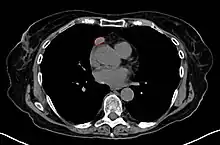

Another axial slice of a CT scan of the chest showing a small thymoma anterior to the heart (marked with the red line).

When a thymoma is suspected, a CT/CAT scan is generally performed to estimate the size and extent of the tumor, and the lesion is sampled with a CT-guided needle biopsy. Increased vascular enhancement on CT scans can be indicative of malignancy, as can be pleural deposits.[1] Limited biopsies are associated with a very small risk of pneumomediastinum or mediastinitis and an even-lower risk of damaging the heart or large blood vessels. Sometimes thymoma metastasize for instance to the abdomen.[5]

The diagnosis is made via histologic examination by a pathologist, after obtaining a tissue sample of the mass. Final tumor classification and staging is accomplished pathologically after formal surgical removal of the thymic tumor.